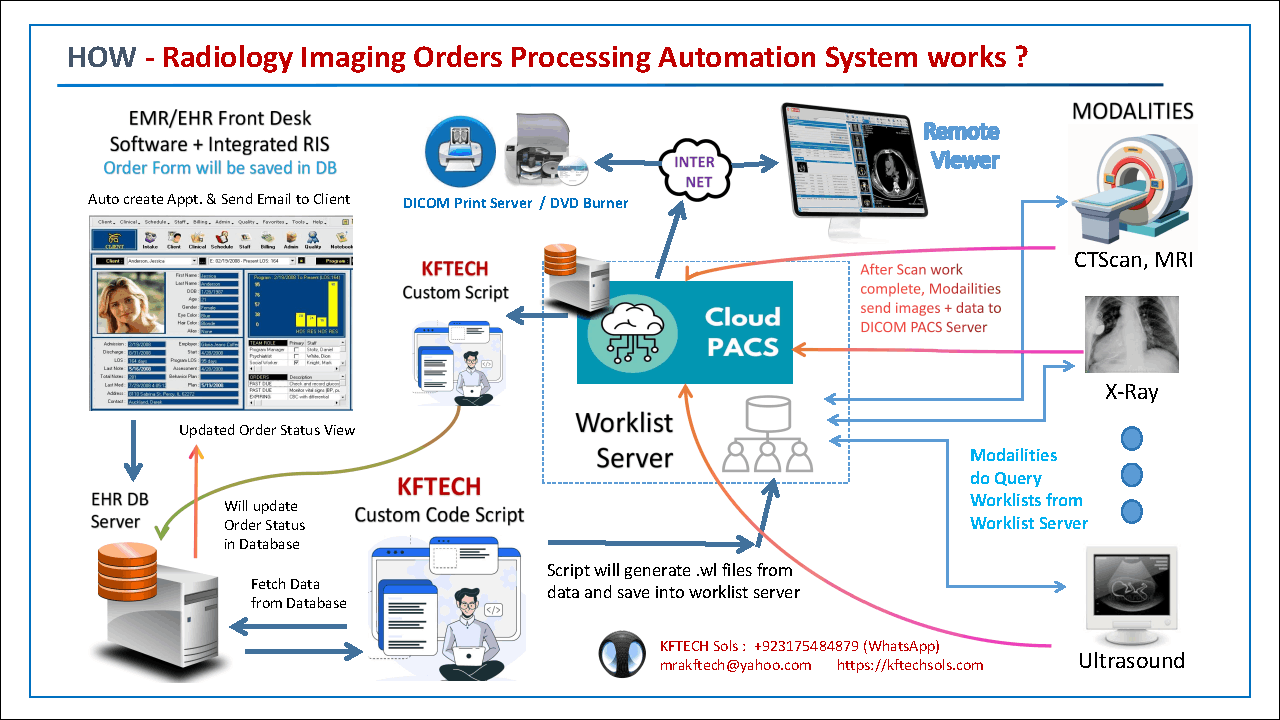

Radiology Imaging Orders Processing Automation Solutions (EMR + Integ. RIS + Worklist + PACS).

The Automatic Radiology Imaging Order Processing System is a unique and comprehensive solution designed to streamline and automate the workflow of radiology services within healthcare facilities like Hospitals and Diagnostic Centers. By integrating Radiology Imaging Order taking Forms directly into the Electronic Health Record (EHR) system, this innovative approach eliminates the inefficiencies of managing separate, disconnected systems.

Key Features :

Seamless Order Management :

When a medical imaging order is placed in the EHR, system automatically generates appointments and notifies clients via email.

Effortless Worklist Creation :

Imaging orders are retrieved from the database, converted into worklist files, and sent directly to the worklist server, allowing modalities to access their tasks without manual intervention.

Scalability

For Medium to Big Size Hospitals / Diag. Centers.

Salient

- Fast, Robust & Auto Imaging Orders Solution